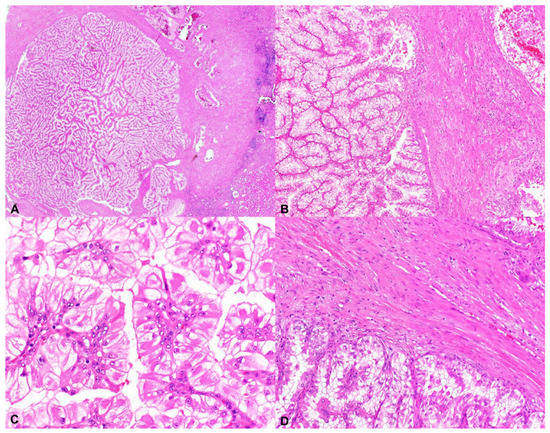

2.1. Tuberous Sclerosis Complex-Associated Papillary Renal Cell Carcinoma (TSC-Associated PRCC)